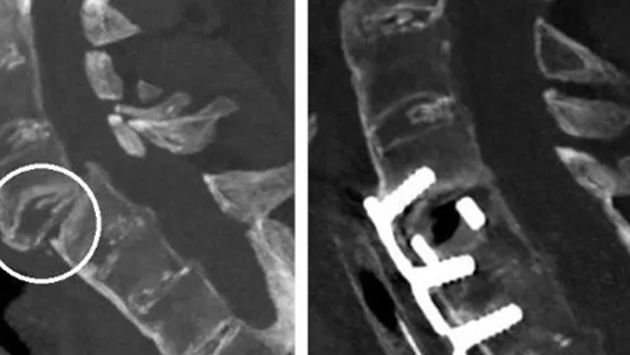

У мужчины диагностировали вывих позвонка в межпозвоночном суставе, перелом и ушиб шейного отдела спинного мозга. Врачи провели открытое вправление вывиха позвонка, скрепили передний шейный спондилодез титановой пластиной и кейджем – то есть соединили соседние позвонки между собой пластиной и винтами. Операция длилась 3,5 часа и прошла успешно.